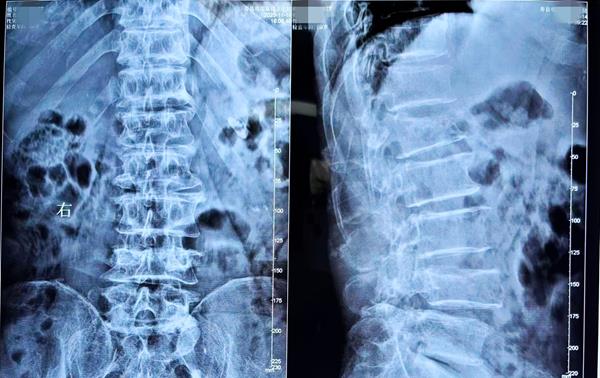

患者术前腰椎部位放射影像(正、侧位)

患者自高处坠落,因轴向暴力导致腰1椎体新近性压缩性骨折、腰4椎体爆裂性骨折、腰4椎体前滑脱(1°)、腰椎管狭窄。